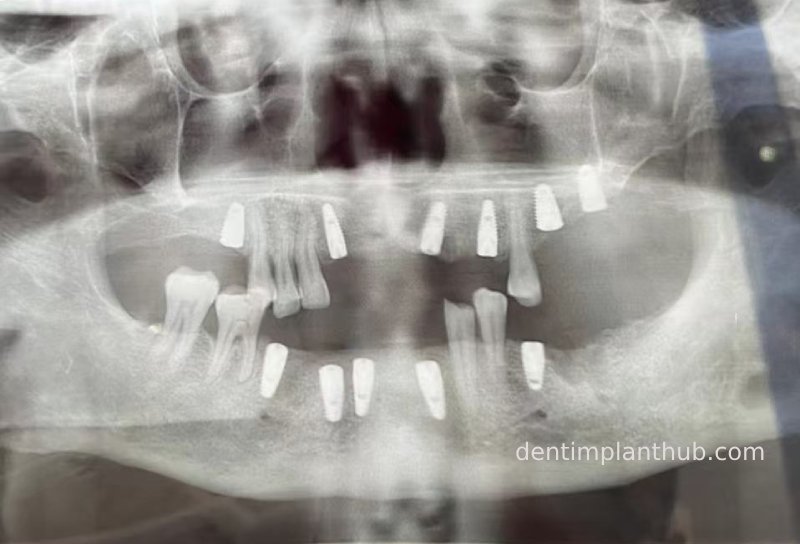

Review panoramic photo from December 24, 2021